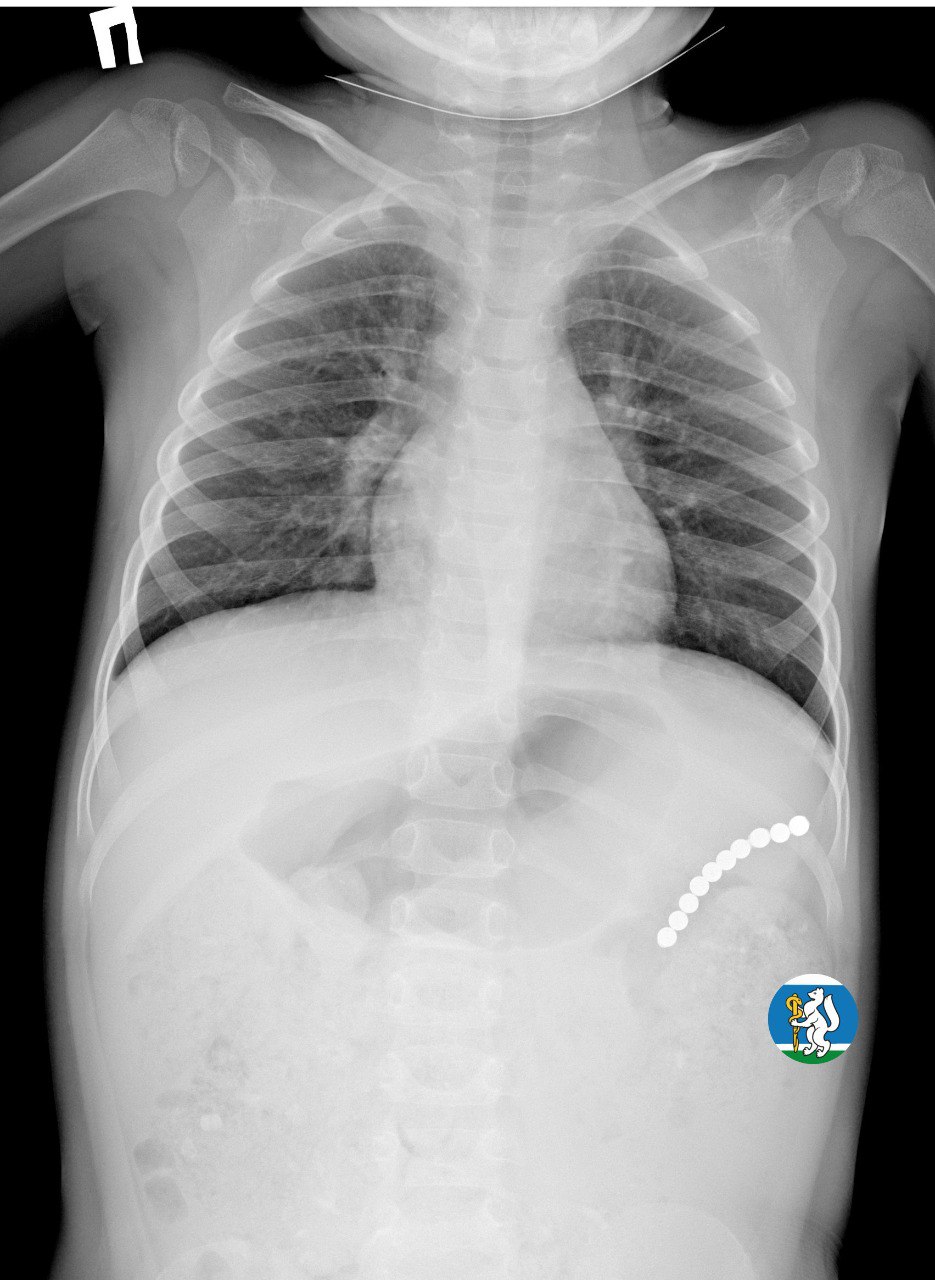

«Малышка почувствовала недомогание, и семья пришла на консультацию к участковому педиатру. Для исключения пневмонии был выполнен рентген органов грудной клетки. Благодаря этому на снимке в проекции желудка диагносты обнаружили чрезвычайно опасный предмет — цепочку магнитных шариков, которые травмировали стенки органов пищеварительной системы и могли стать причиной перитонита. В связи с угрозой жизни Ульяну оперативно госпитализировали в Детскую городскую клиническую больницу №9, где ей оказали всю необходимую помощь», — рассказала глава ведомства.

«Для минимизации риска осложнений удаление инородных тел было проведено интраоперационно. В ходе вмешательства дежурная бригада врачей извлекла 10 магнитных шариков, цепочка которых в длину составила 5 сантиметров», — рассказал детский хирург ДГКБ №9 Андрей Чукреев.